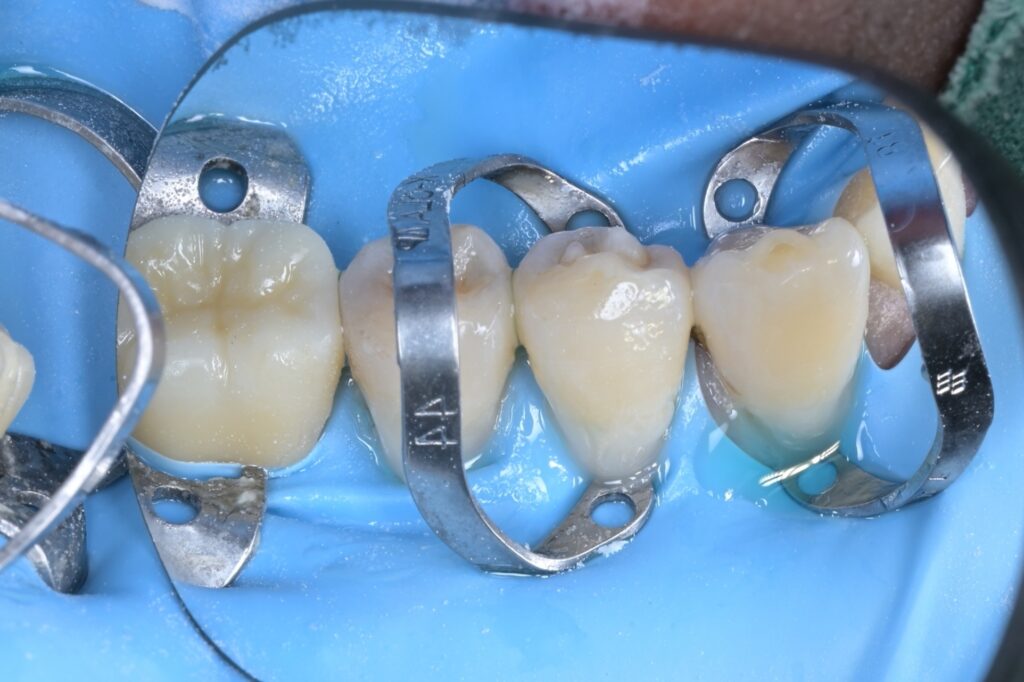

STEP 6. 정밀 레진 빌드업

확보된 시야를 바탕으로 송곳니와 작은 어금니도 꼼꼼하게 레진을 쌓아 올립니다. 치아 사이사이의 미세한 틈까지 놓치지 않고 원래 모양대로 복원합니다.